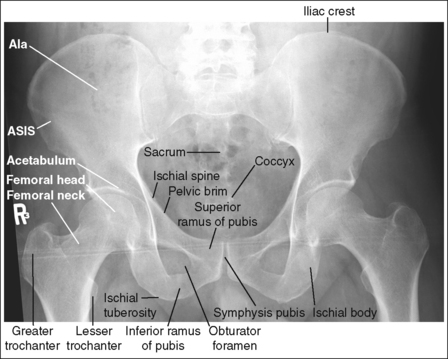

Hip: Axiolateral (Inferosuperior) Projection (Danelius-Miller Method)

See Figure 7-15 and Box 7-4.

Scatter radiation is controlled. The proximal femur demonstrates uniform density across it.

• Tight collimation and placement of a flat lead contact strip or the straight edge of a lead apron over the top, unused half of the IR, as shown in Figure 7-16, also prevent scatter radiation from reaching the IR.

• Compensating filter. Frequently, when an exposure (mAs) is set that adequately demonstrates the hip joint, the proximal femur is overexposed because of the difference in body thickness in these two regions. A wedge-type compensating filter attached to the x-ray tube can be used to obtain uniform image density of the hip joint and proximal femur. Align the thin end of the filter with the femoral neck and the thicker end with the proximal femur.

The femoral neck is demonstrated without foreshortening. The proximal aspects of the greater and lesser trochanters are demonstrated at approximately the same transverse level.

• An axiolateral projection of the hip is obtained by placing the patient on the imaging table in an AP projection, with the unaffected hip positioned next to the lateral edge of the table. Flex the patient's unaffected leg until the femur is as close to a vertical position as the patient can tolerate, and then abduct the leg as far as the patient will allow. Support this leg position by using a specially designed leg holder or suitable support. Flexion and abduction of the unaffected leg move its bony and soft tissue structures away from the affected hip. Inadequate flexion or abduction of the unaffected leg results in superimposition of soft tissue onto the affected hip, preventing visualization of the affected hip (see Image 12).

• IR placement. Once the patient's unaffected leg has been positioned, place the grid IR against the patient's affected side at the level of the iliac crest (Figure 7-16). To demonstrate the affected femoral neck without foreshortening, align the x-ray tube horizontally with the central ray perpendicular to the femoral neck and adjust the distal end of the IR until the receptor's long axis is perpendicular to the central ray and parallel with the femoral neck.

• Localizing the femoral neck for central ray alignment. To localize the affected femoral neck, first find the center of an imaginary line drawn between the superior symphysis pubis and the ASIS. Then, bisect that line by drawing a perpendicular line distally (Figure 7-17). This imaginary line parallels the long axis of the femoral neck as long as the leg is not abducted. Once the long axis of the femoral neck has been located, align the central ray perpendicular to it and the IR parallel with it.

FIGURE 7-17 Locating the femoral neck and proper image receptor placement for small and average patients.

• Effect of central ray and femoral neck misalignment. Misalignment of the central ray with the femoral neck results in femoral neck foreshortening and a shift in the transverse level at which the greater trochanter is located. If the angle formed between the femur and the central ray is too large, the proximal greater trochanter is demonstrated proximal to the transverse level of the lesser trochanter and is superimposed by a portion of the femoral neck (see Image 13). If the angle between the femur and the central ray is too small, the proximal greater trochanter is demonstrated distal to the transverse level of the lesser trochanter. This mispositioning seldom occurs, because the imaging table and tube position prevent such a small angle.

The lesser trochanter is in profile posteriorly, and the greater trochanter is superimposed by the femoral shaft.

• Rotation of the patient's affected leg determines the relationship of the lesser and greater trochanter to the proximal femur on an axiolateral hip projection. In general, when a patient is placed on the imaging table and the affected leg is allowed to rotate freely, it is laterally (externally) rotated.

• Effect of leg rotation on proximal femur visualization. To position the proximal femur in a lateral projection (90 degrees from the AP projection), demonstrating the lesser trochanter in profile posteriorly and superimposing the greater trochanter by the femoral shaft, the affected leg must be internally rotated until an imaginary line drawn between the femoral epicondyles is positioned parallel with the imaging table. The patient's foot is angled internally 15 to 20 degrees from a vertical position (Figure 7-18). If the affected leg is not rotated internally, the greater trochanter is demonstrated posteriorly and the lesser trochanter is superimposed over the femoral shaft (see Image 14). How much greater trochanter is demonstrated without femoral shaft superimposition depends on the degree of external rotation. Greater external rotation increases the amount of greater trochanter shown.

IMAGE 14

• Positioning for a proximal femoral fracture or dislocation. When a patient has a dislocated hip or a suspected or known proximal femoral fracture, the leg should not be internally rotated, but left as is. Forced internal rotation of a dislocated hip or fractured proximal femur may injure the blood supply and nerves that surround the injured area. Because the patient's leg is not internally rotated in such cases, it is acceptable for the greater trochanter to be demonstrated posteriorly and the lesser trochanter to be superimposed over the femoral shaft (see Image 15).

IMAGE 15

The femoral neck is at the center of the exposure field. The acetabulum, femoral head and neck, greater and lesser trochanters, and ischial tuberosity are included within the collimated field. Any orthopedic apparatus should be included in its entirety.

• Center a perpendicular central ray to the patient's midthigh, at the level of the femoral neck, to place it in the center of the exposure field. The center of the femoral neck is located at a level 2.5 inches (6.25 cm) distal to the midpoint of a line connecting the ASIS and superior symphysis pubis. Open the longitudinal collimation the full length of the IR. Transversely collimate to within 0.5 inch (1.25 cm) of the proximal femoral skin line.

• A 10- × 12-inch (24- × 30-cm) IR placed lengthwise should be adequate to include all the required anatomic structures. A larger IR and lower centering point may be necessary to include hip orthopedic apparatus (Figure 7-19).

• IR placement alternative. The level at which the IR is placed along the patient's lateral body surface determines whether the acetabulum and femoral head are included on the IR. For patients with minimal lateral soft tissue thickness, the upper IR edge should be firmly placed in the crease formed at the patient's waist, just superior to the iliac crest (see Figure 7-17). For patients with ample lateral soft tissue thickness, the upper IR edge needs to be positioned superior to the iliac crest (Figure 7-20). This superior positioning will result in magnification because of the increase in the object–image receptor distance (OID) but is necessary if the acetabulum and femoral head are to be included on the axiolateral hip projection.